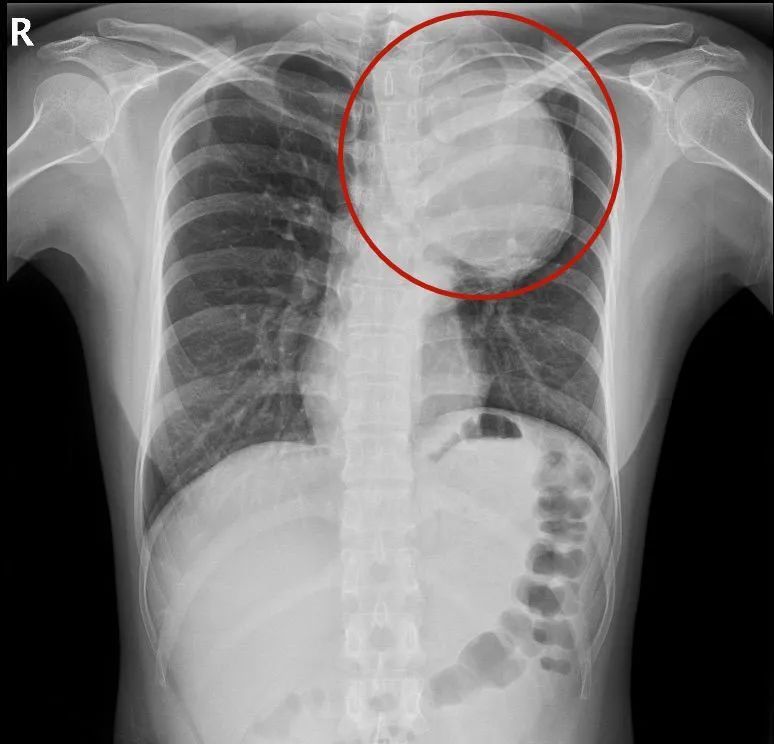

“患者的胸主动脉瘤非常大,位于主动脉弓降部,它会像吹气球一样,越长越大。正常人的主动脉弓部只有香肠那么大,而患者的主动脉瘤直径达75mm,已经有大青芒那么大了,是正常人的5倍,瘤子像一条蟒蛇一样,从颈部长到膈肌,深入隐藏在患者体内。”南方医科大学深圳医院心脏与血管外科主任杨建安说。

小茹的胸主动脉瘤已经是正常人的5倍,血管壁已经被撑得很薄,管壁只有1mm,随时可能破裂,血压一旦升高,比如生气、解大便、跑步等,都可能引起瘤子破裂,必须马上拆弹。